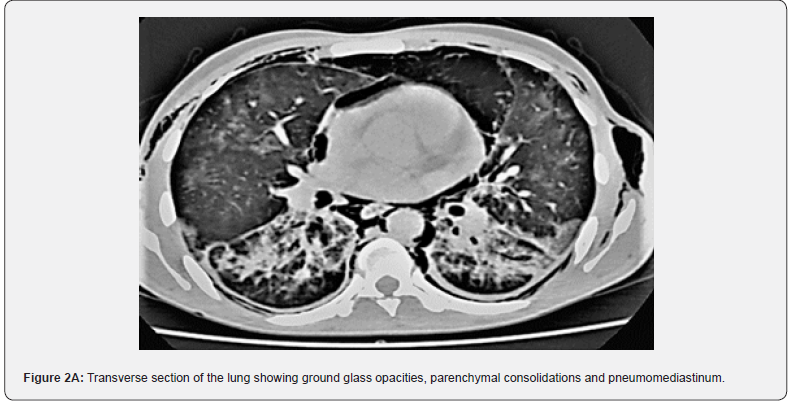

A 30-year-old man was admitted to the emergency room for stage 3 dyspnoea of the MRC classification, with signs of chest muscle tightness, fever at 39° and sweating. After conditioning and stabilizing the patient on the ventilatory level, the physical examination showed crackles on pulmonary auscultation, heart sounds were well perceived, there was no abnormality in the rest of the ‘physical examination. Oxygen saturation was low at 89% in room air. Blood pressure was 110/08mmHg. Chest x-ray showed diffuse nodular opacities in both lung fields as well as reticular lines (Figure 1). Chest CT showed left basal consolidation and scattered ground glass hyper densities in both lungs (Figure 2A and 2B). The biological assessment showed white blood cells at 13,000 e/mm3, a CRP at 100mg/l. A rapid test for positive HIV infection that has been confirmed by serology after patient consent. Normal liver and kidney function.

The realization of the thoracic scanner is often necessary especially if the patient presents a chronic pathology, or if there is a suspicion of oesophageal rupture. It shows the pneumomediastinum in a precise way where air is detected over the entire anatomical tract of the mediastinum [16]. Esophageal transit with water-soluble fluids is necessary if there is a suspicion of esophageal rupture, it shows extravasation of the contrast product. The evolution of spontaneous pneumomediastinum is generally towards resorption in 48 to 96 hours by the passage of air into the bloodstream, this passage is accelerated if the patient is put on oxygen thanks to the theory of the diffusion of nitrogen [17]. The management of pneumomediastinum depends on the severity of the clinical presentation and the volume of it on the chest CT scan, as well as possible complications which may be compression of adjacent structures or air infiltration to the different spaces. life-threatening.